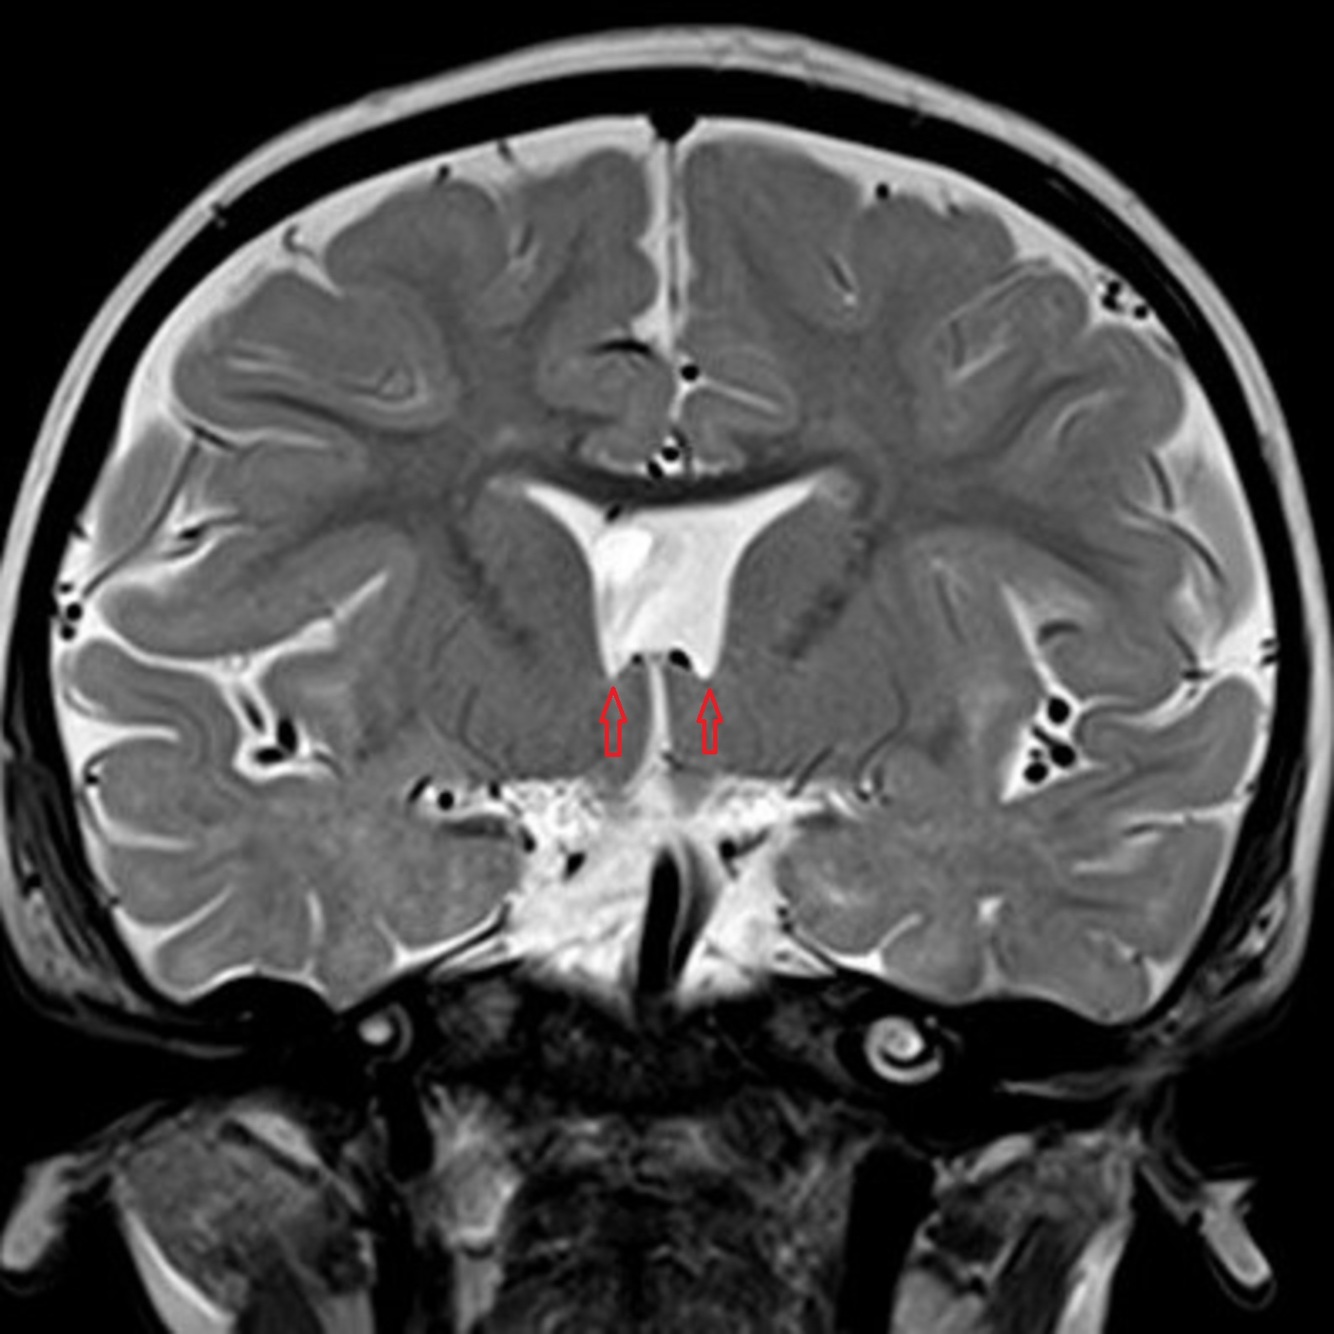

Selected image of coronal T2-weighted sequence showed point-down appearance of the anterior horns of the bilateral lateral ventricles (red arrows).

Hypoplastic optic nerves and chiasm, absence septum pellucidum with resultant typical configuration of the anterior horns of the lateral ventricles, along with ectopia of the posterior pituitary gland. On the other hand, the globes are intact and the olfactory bulbs are present with no evidence of associated parenchymal abnormality.